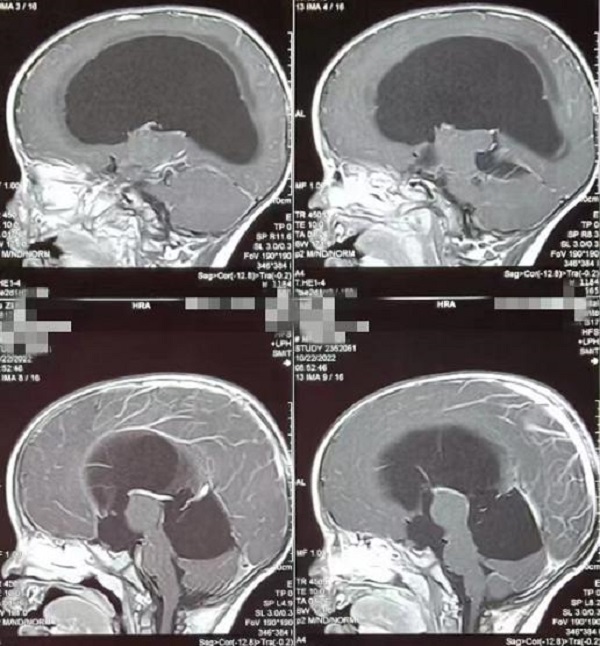

一岁多的赫赫小朋友自出生头颅就比同龄小孩大,近半月来进食后出现呕吐,伴头痛,在当地医院及省内多家医院治疗不见好转,于是来到陕健医二一五医院神经重症监护室,因患儿近半月多不能正常进食,入院时精神萎靡,头颅MRI检查提示“脑室系统扩大,双侧脑室额角周围间质水肿,左侧丘脑占位病变,鞍上池及小脑上池扩大”。

为进一步鉴别脑积水类型,行磁共振3D FIESTA序列检查可见侧脑室扩大明显,中脑导水管中段阻塞、三脑室底受压下陷,诊断梗阻性脑积水。